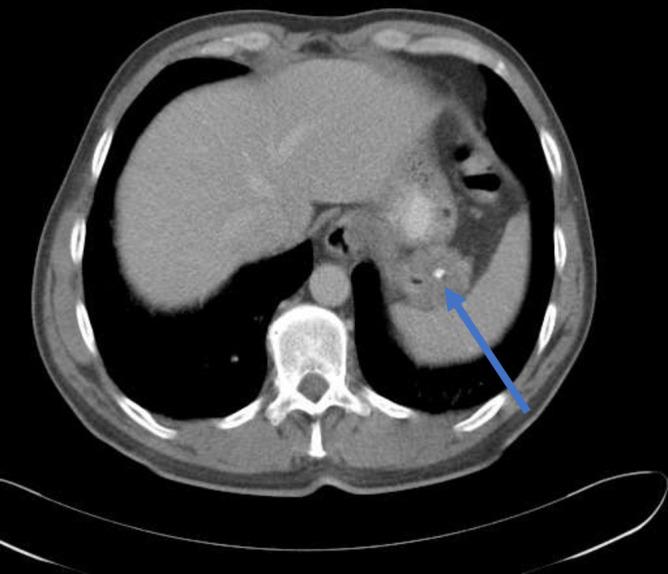

We report a case of a 54-year-old man who developed an atypical systemic syndrome involving Raynaud's phenomenon, pulmonary fibrosis and skin thickening. These features were initially suggestive of newly diagnosed scleroderma. However, he displayed atypical clinical features of same, antinuclear antibody was negative and symptoms were refractory to various immunosuppressive therapies. CT imaging revealed a gastric mass, which later proved to be a gastrointestinal stromal tumour (GIST). Resection of the GIST leads to minimal symptomatic improvement. Surveillance imaging 1 year later revealed metastatic deposits. He was subsequently initiated on imatinib therapy, which led to a rapid improvement in fibrotic changes within weeks. While there have been previous descriptions of paraneoplastic fibrotic disorders, this is the first description of a scleroderma mimic in the setting of a GIST. It highlights an important potential overlap in the pathogenesis of these disease processes and the potential efficacy of tyrosine kinase inhibitors for scleroderma-like fibrotic disorders.

我们报告了一例 54 岁男性,他出现了一种非典型的全身综合征,涉及雷诺现象、肺纤维化和皮肤增厚。这些特征最初提示为新诊断的硬皮病。然而,他表现出同样的非典型临床特征,抗核抗体阴性,且症状对各种免疫抑制治疗均无反应。CT 成像显示胃内有一个肿块,后来证实是胃肠道间质瘤(GIST)。切除 GIST 导致症状有轻微改善。1 年后的监测成像显示有转移病灶。随后他开始接受伊马替尼治疗,数周内导致纤维化改变迅速改善。虽然之前有描述过副肿瘤性纤维性疾病,但这是首例 GIST 中硬皮病样表现的描述。这突出了这些疾病过程在发病机制上的重要潜在重叠,以及酪氨酸激酶抑制剂对硬皮病样纤维性疾病的潜在疗效。